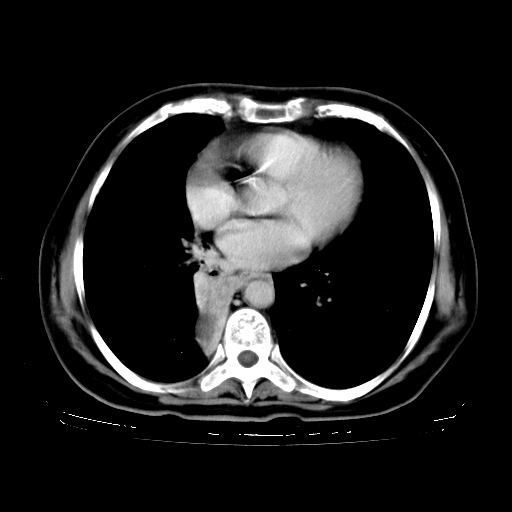

标题: CT23067:女,70岁,咳嗽、咳痰一个月,低热一周。 [打印本页]

女,70岁,咳嗽、咳痰一个月,低热一周。

1.左上肺结核,部分纤维化。右肺中下叶部分肺不张,内见液化、坏死及点状钙化,右中下叶支气管壁增厚、管腔狭窄,见多个点状钙化,结合临床考虑支气管内膜结核,建议痰检查抗酸杆菌并参考血沉。两肺多个小圆点状高密度灶,境界模糊,多考虑结核肺内播散。但本人年龄较大首先应支气管镜检以除外右肺癌。

2.胸主动脉夹层。

1、右肺占位,考虑周围型ca 。

2、右下肺软组织密度肿块影,考虑肺隔离征。

3、两肺肺结核(右肺下叶背段及左肺)。

4、主动脉夹层。

5、右侧少量胸腔积液。